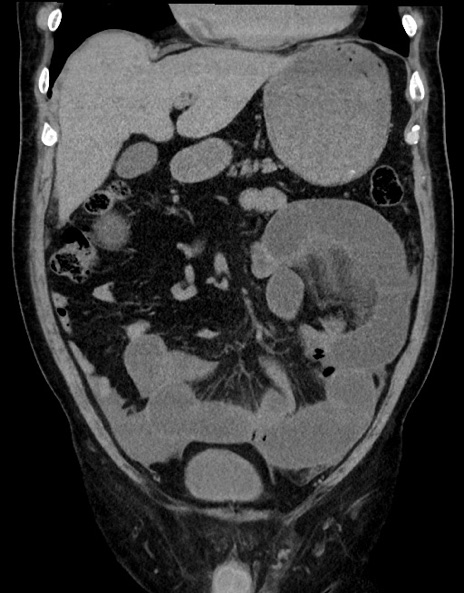

症例15(冠状断像)

【症例】70歳代男性

【主訴】腹痛

【現病歴】今朝から腹痛あり。全体的に痛い。特に左上の方。排ガスが今日はない。冷や汗が出る。

【既往歴】直腸癌術後

【身体所見】左側腹部〜上腹部に圧痛あり。腹膜刺激症状明らかなではない。軽度反跳痛。左下腹部に術後瘢痕あり。